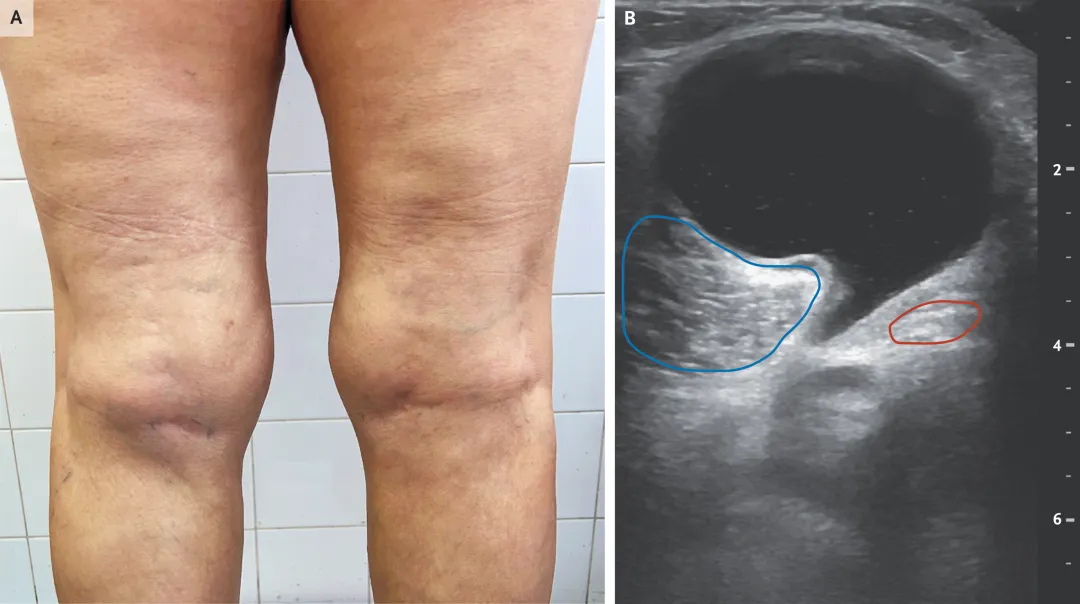

查体特写(图A):请注意看患者的左侧腘窝(膝盖后方)。当我们让患者站立并完全伸直膝关节时,一个明显的肿块就突显出来了。

如果说查体只是怀疑,那么超声就是确诊。NEJM这张超声图(图B)完美展示了那个让我们 “司空见惯却又充满深意”的征象 — “ 对话气泡征(Speech Bubble Sign)”:气泡主体,巨大的、黑色的(无回声)囊体,充满了关节液。

气泡的嘴(颈部):这是最关键的细节!囊肿向深部延伸出一个细长的“颈”,钻进了两个肌肉之间。

上方(浅层):腓肠肌内侧头(蓝色圈)。

下方(深层):半膜肌肌腱(红色圈)。